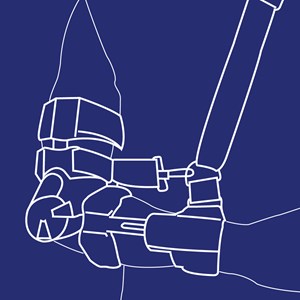

Albueortose (EO – Elbow Ortose)

Type: pdf

Størrelse: 1236 KB